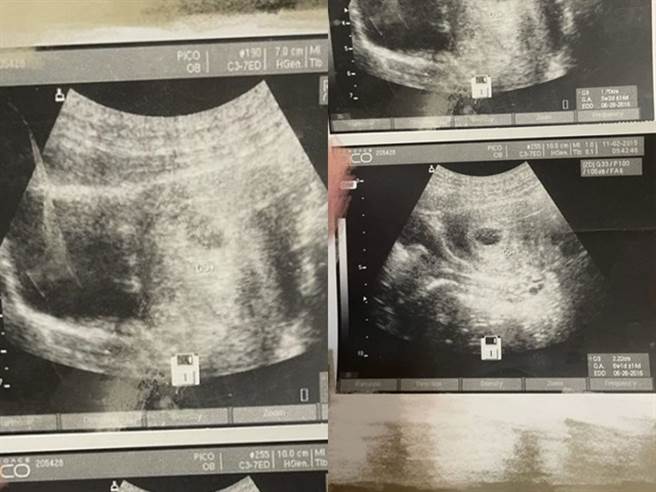

网友在男友房间找到1本男友与前女友的生活小本子,里头纪录着男友与前女友的感情点滴,不过某1页内页竟夹着2张「胎儿超音波照」。(图/翻摄自Dcard)

该女友在未询问男友前,已先PO文在Dcard上询问网友意见,网友们则纷纷留言说「如果你觉得无论如何你都要和他共度一生,不会因为其他事改变你的想法,那更要问啊,总比你一直放在心上好」、「如果是我既然发现了应该会问欸」、「下面这张有胎囊了,6周的大小」、「我觉得就问!搞不好是家人的」。